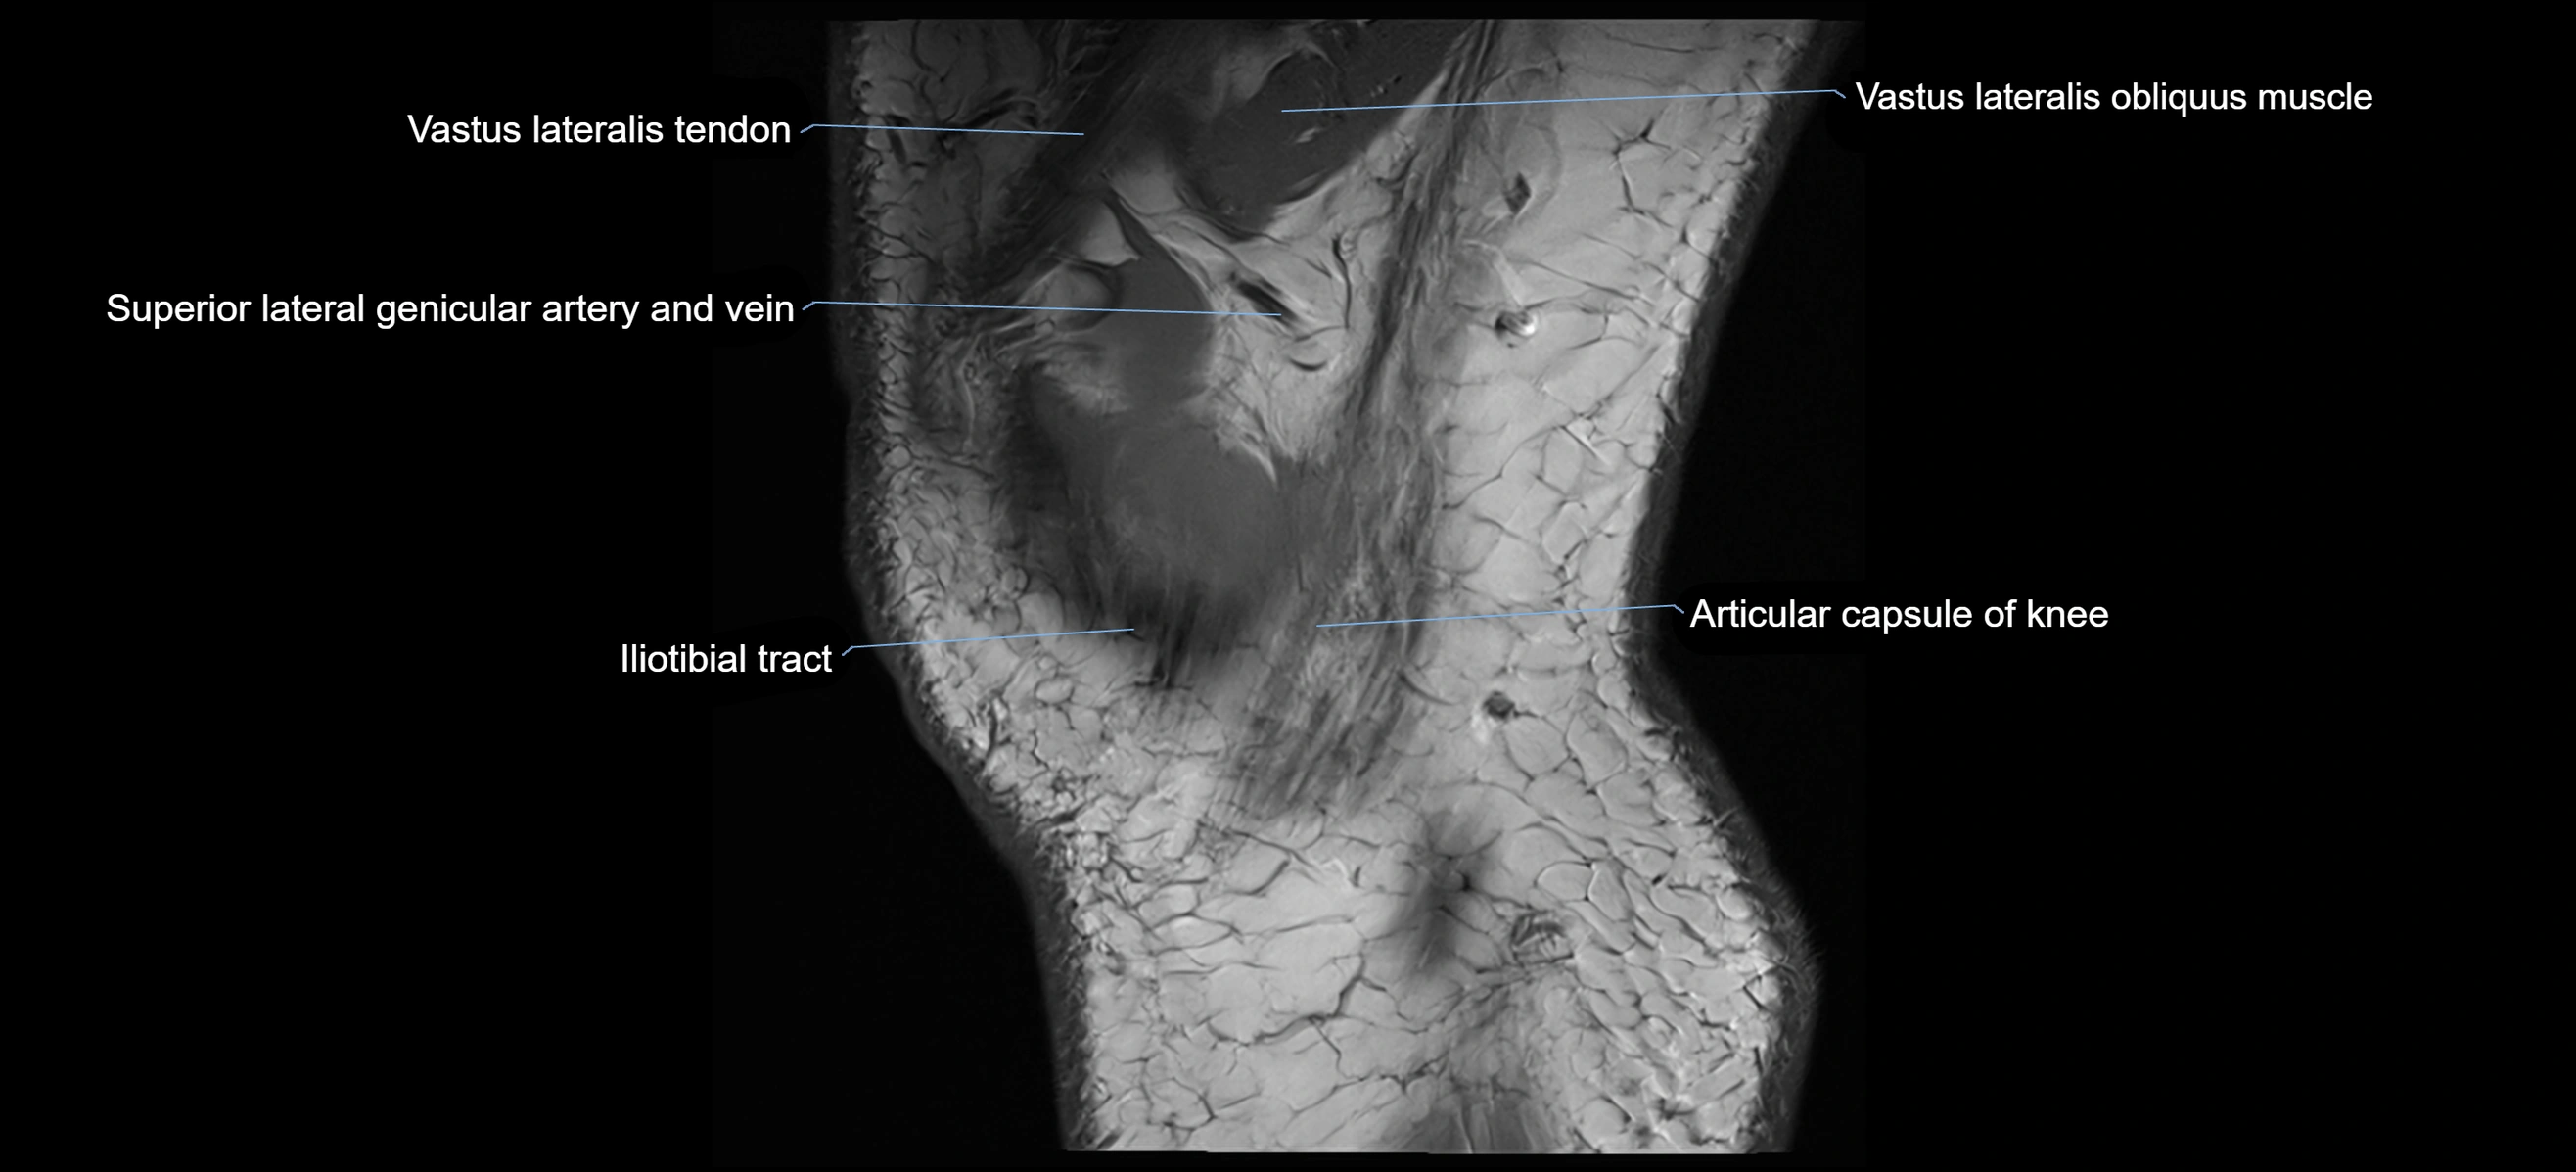

- Distal vastus lateralis tendon

- Superior lateral genicular artery

- Superior lateral genicular vein

- Trochlear groove

- Vastus Lateralis Obliquus Muscle